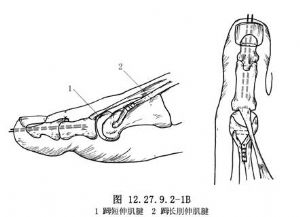

10.2 2.Hibbs手术(趾长肌腱转位于第3楔状骨)